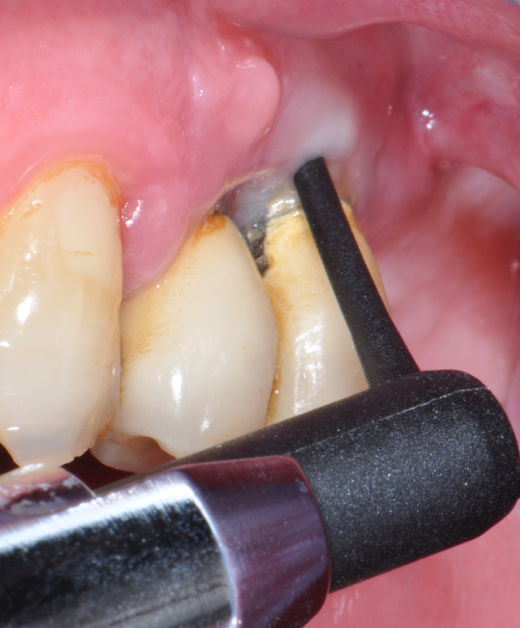

The parameters used to define peri-implant disease usually are: Probing Depth (PD), Crestal Bone Loss (CBL), Bleeding on Probing (BOP) and presence of suppuration and/or fistula.9 Peri-implant mucositis is characterised by soft tissues inflammation witnessed by BOP with or without PD deepening but no effects on the crestal bone while peri-implantitis is characterised by CBL, BOP alone or in conjunction with pus, with or without PD deepening. (Figs. 1, 2 and 3) display the diagnostic steps of a case of peri-implantitis. While mucositis allows a complete healing, peri-implantitis is not reversible.12

Fig.2: Case 1. BOP starts immediately after probing.